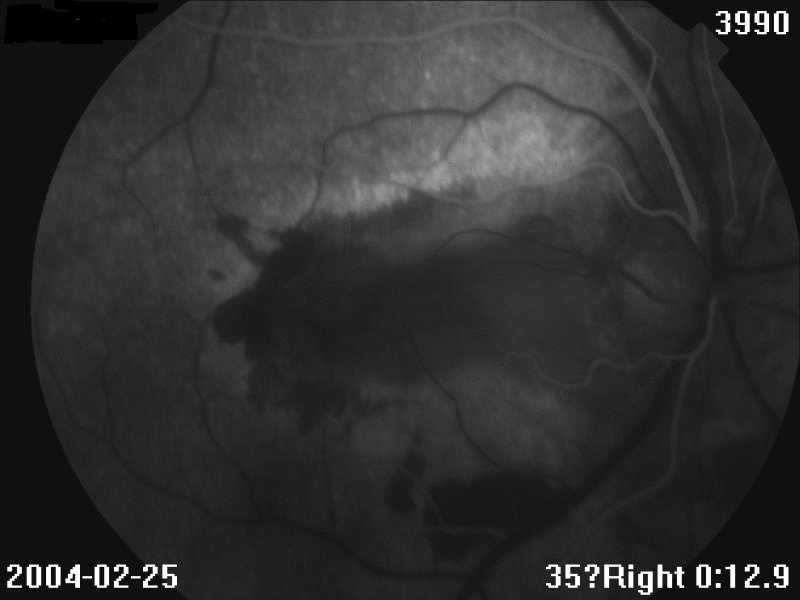

眼底见:玻璃体尘状混浊 眼底图 右眼 左眼 荧光造影图 眼科B超 OCT 视野 讨论: 1、诊断及鉴别诊断

2、眼底见病灶起自视乳头,葡行性发展,呈地图状,界清

3、有CNV,表现为网膜下出血、渗出

4、FFA:早期低荧光,晚期高荧光;有荧光渗漏(CNV)、遮挡荧光(出血)

FFA:早期低荧光,晚期高荧光;如有CNV,可见荧光渗漏,或出血遮挡荧光。晚期病例:病灶边缘高荧光,中央低荧光,经常见大的脉络膜血管